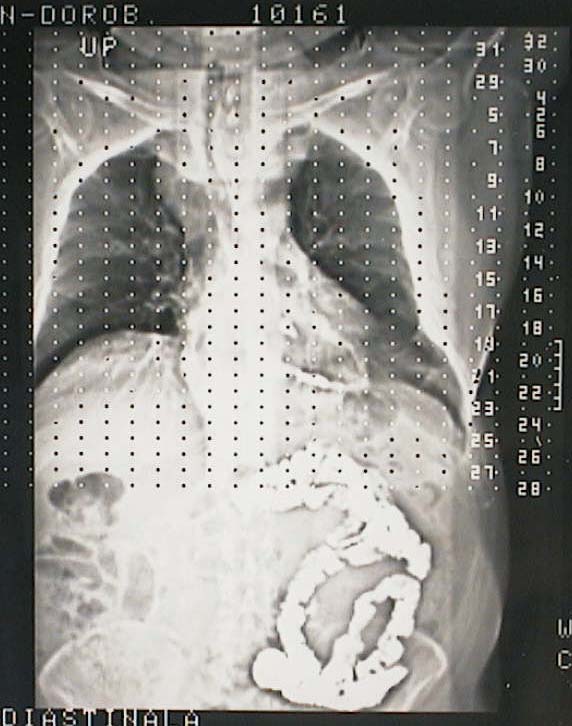

Chest Radiography: inhomogenous opacity of the upper third of the thorax.

Radiografia de torace: opacitate neomogenă a 1/3 superioare a toracelui.